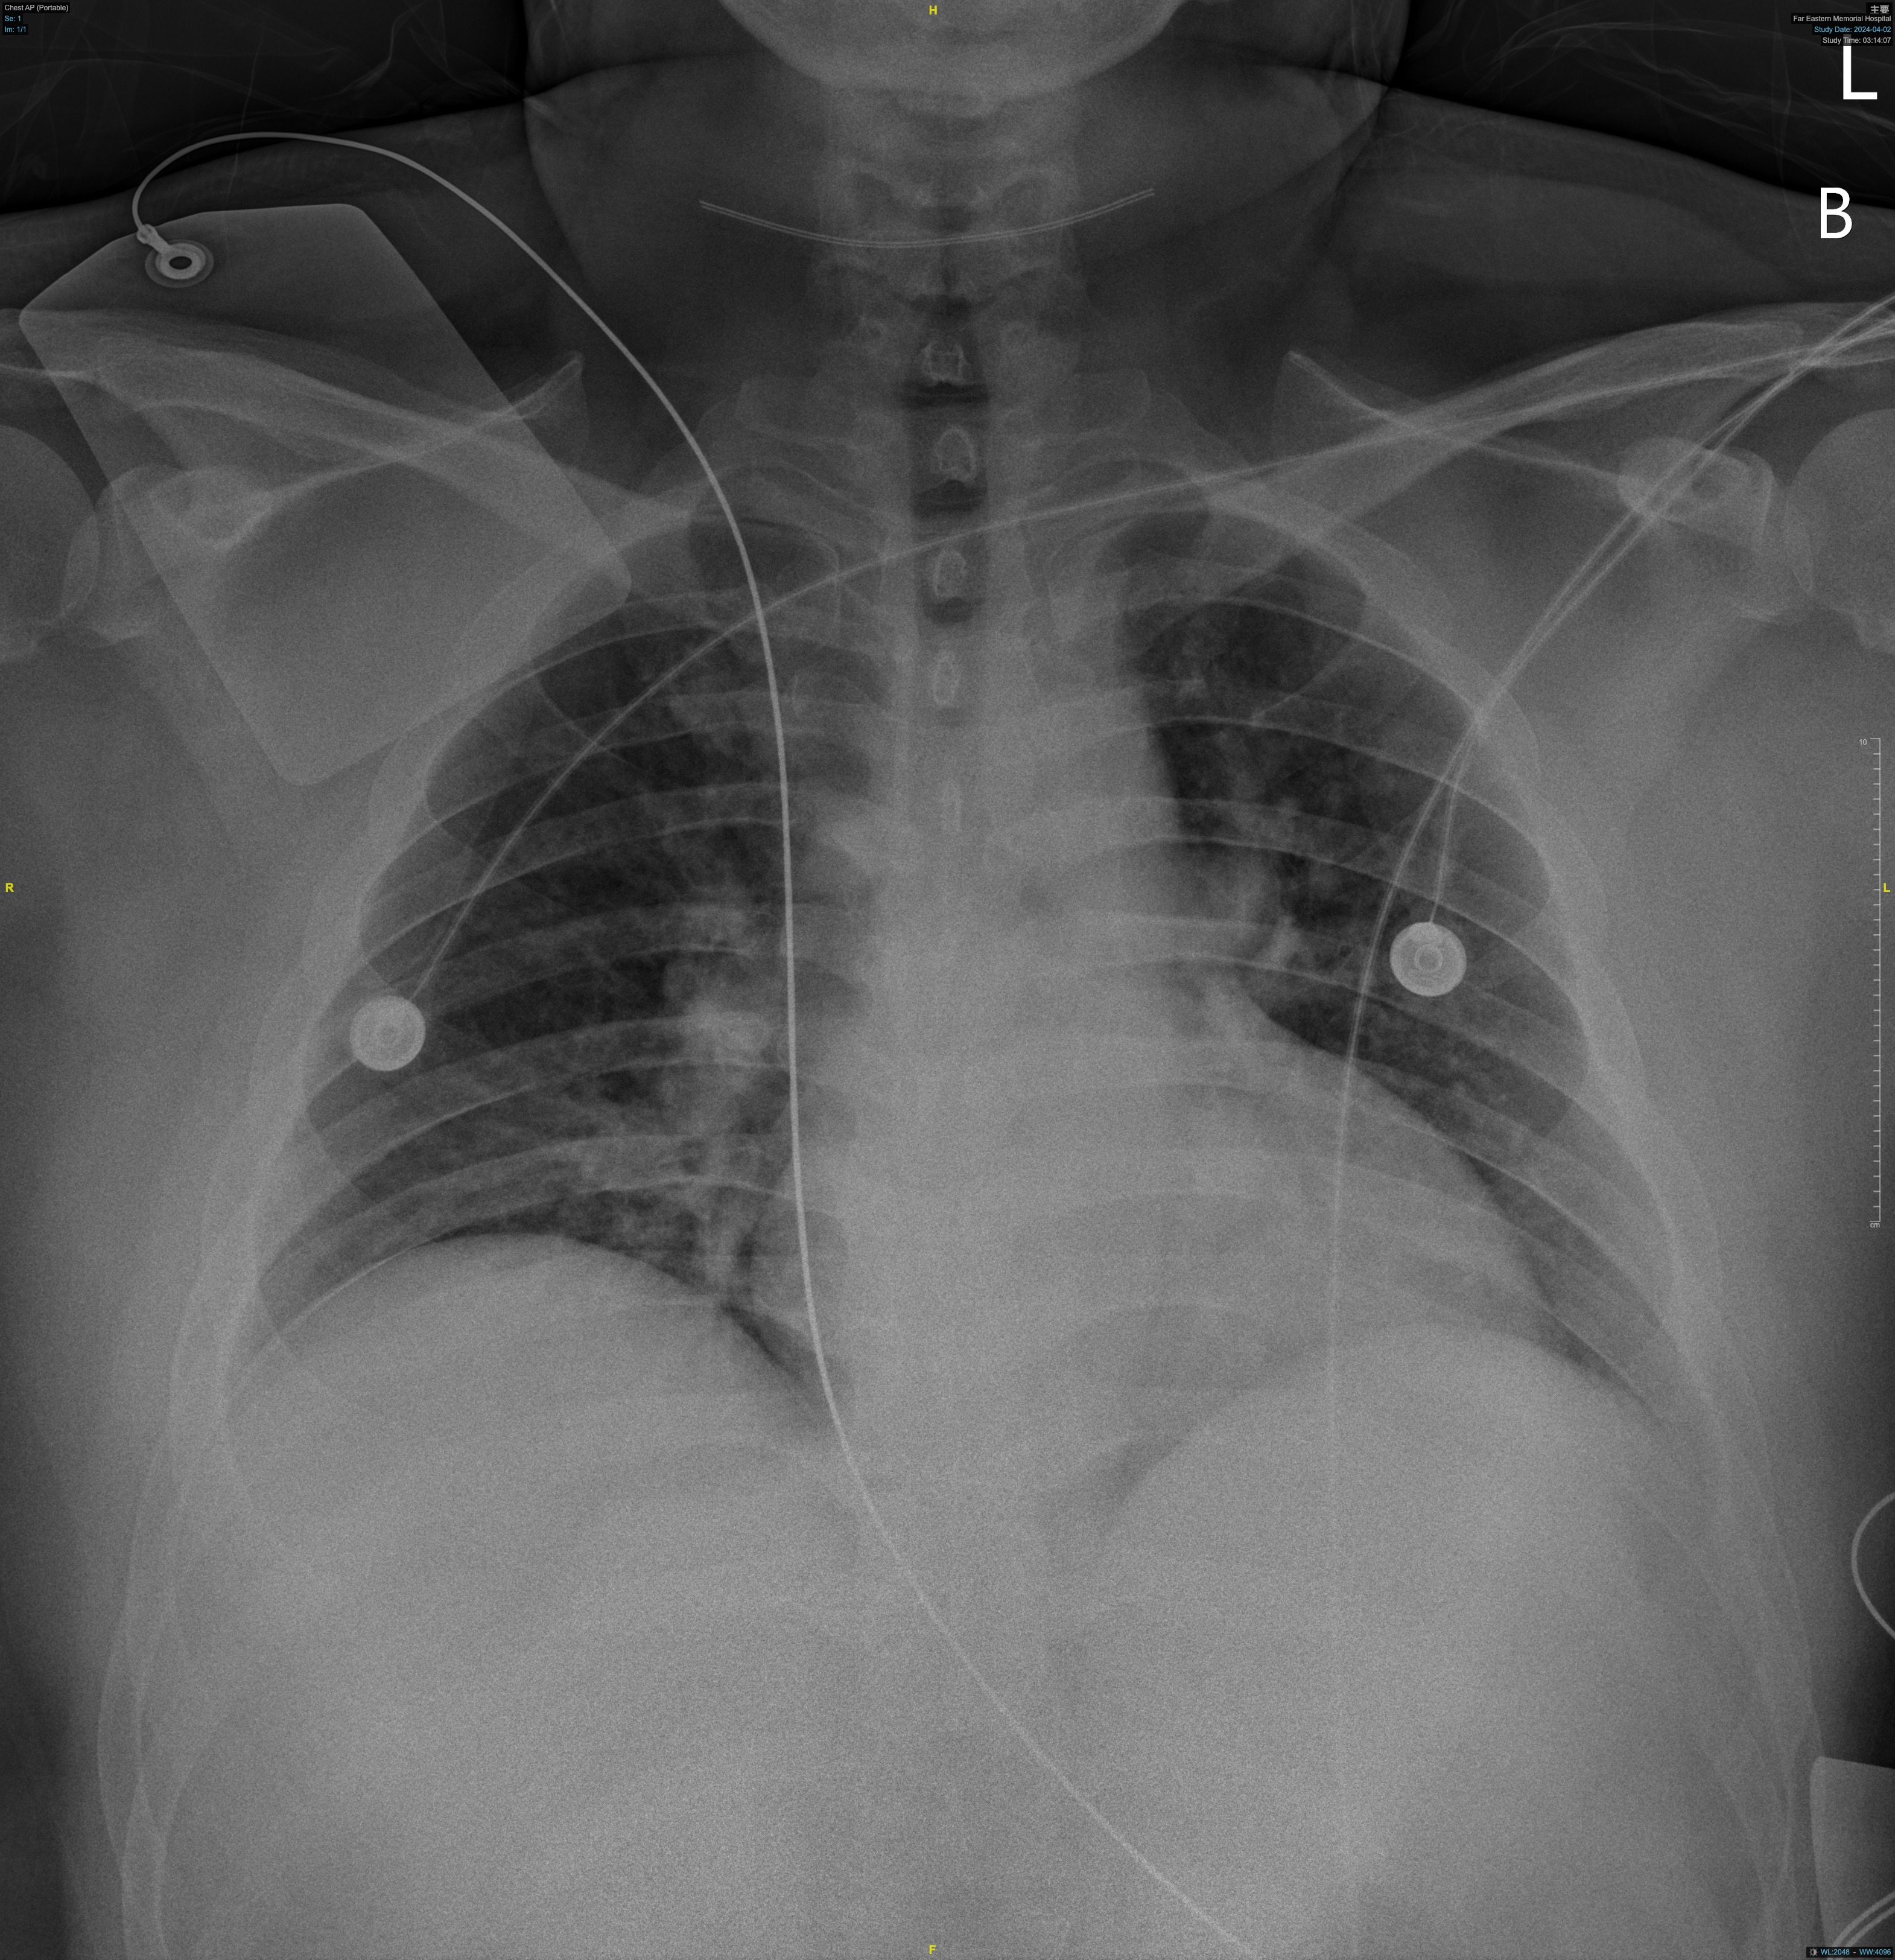

During this emergency catheterization, the right radial artery was accessed using a 20-gauge needle. A 6 Fr in 5 Glidesheath Slender® (Terumo Corp., Tokyo, Japan) was inserted. Coronary angiography was performed using Terumo 5 Fr Judkins catheters, revealing in-stent total occlusion of the RCA and patent left coronary artery (LCA).